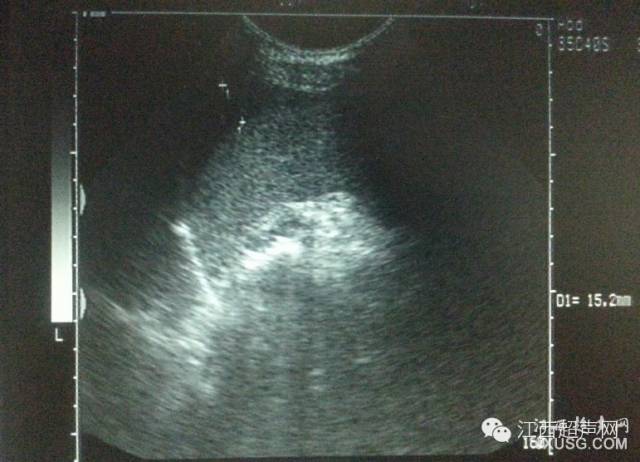

51.检查妇科、膀胱,膀胱需要适当充盈,强调“适当”。看看这个膀胱,是不是很像后壁的病变?

彩超伪像是什么60个超声诊断中容易误诊的正常结构_https://www.jmylbn.com_新闻资讯_第10张